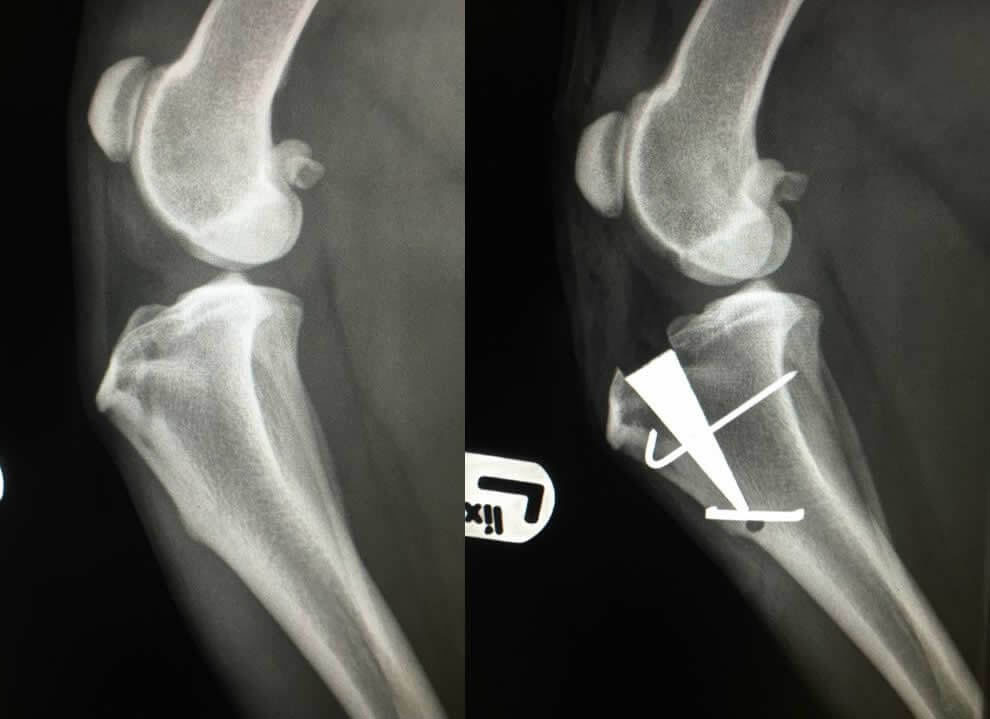

Enter the Modified Maquet Preocedure, aka, MMP, developed in England and first introduced in the US in 2014. The MMP procedure utilizes the same principles as the TTA, however, with less cumbersome hardware, smaller incision, and shorter surgical time. The wedge that is placed within the bone does not require multiple screws to be placed into the bone as the TTA and TPLO hardware does. Once placed, it simply requires the placement of one single pin and and staple that effectively hold the hardware in place. What’s more, the MMP wedge is made of a porous titanium alloy that allows bone to grow through it. This results in much faster recovery times of 4-6 weeks (as opposed to TPLO and TTA that are 10-12 weeks). See the images below for a post operative MMP x-ray and an image of the actual hardware used in the procedure:

Let’s return to TPLO for one moment before I close. Remember I wrote about converting the sheer force into a compressive force? No, it is not painful and, yes, it stabilizes the knee, but it is not without consequence. Over time that compressive force leads to earlier stage degenerative joint disease of knees surgically repaired via TPLO as compered to TTA and MMP. Also, look back at the TPLO x-ray and oberve the metal structures across the surface of the leg….those are skin staples necessary to close the skin and give you an idea of the size of the incision. That represents an 8-10 inch incision versus MMP that requires typically no more than a 3-4 inch incision.

I am enjoying quicker return to function, by far faster recovery times, and excellent results with the MMP procedure for repair of the CCL in dogs that I have been performing the surgery for since completing the training. The standard TTA and TPLO remain good procedures especially in the hands of an experienced veterinary surgeon, but in my view, MMP is currently the best CCL repair procedure for dogs over 38 pounds that have suffered CCL tears.